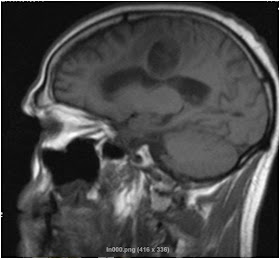

Varón de 46 años intervenido hace 10 meses (glioblastoma parietal derecho). Exéresis macroscópicamente completa. Radioterapia concomitante+metozolamida. Ingresa por crisis epiléticas.